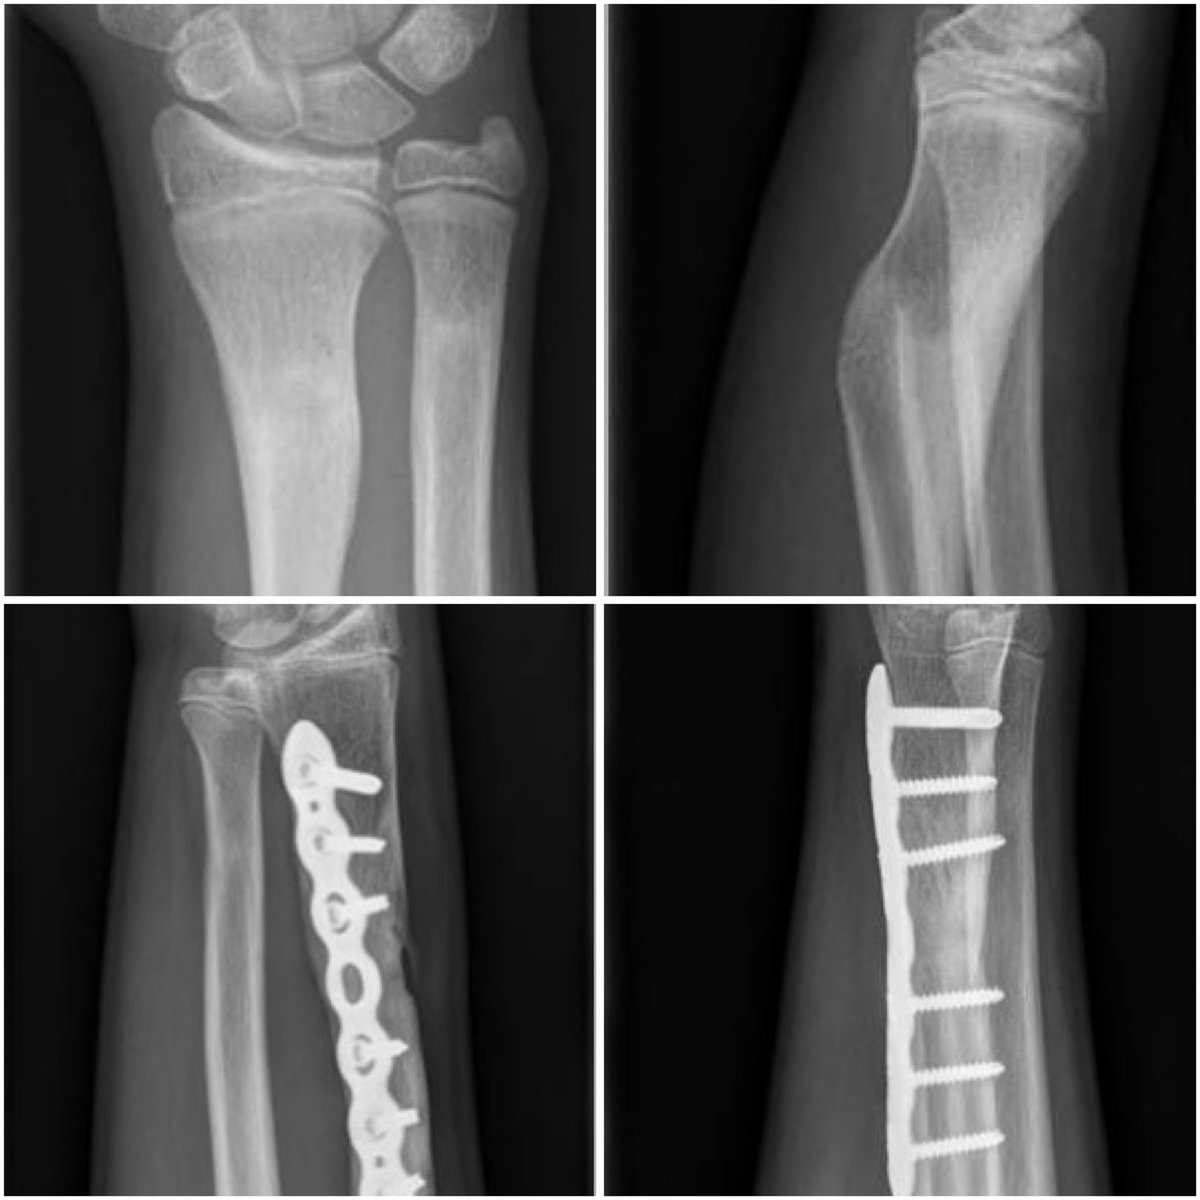

Surgeon in training| PhD trauma surgery| in-hospital medical #3Dprinting| European Surgical technical innovation award| 3Dlab Sierra Leone #3Dsurgery